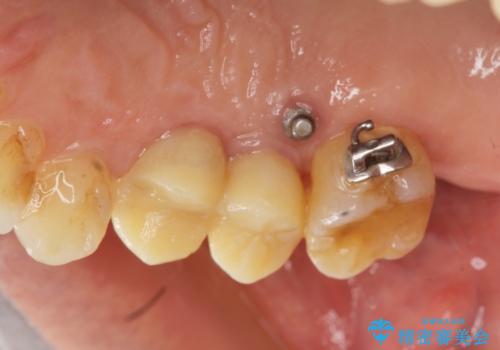

連結補綴について

特定の歯に強く力がかかりまた歯周病により臨床歯根が短くなっているような場合、歯の動揺を抑えるため連結補綴が検討されます。

歯の動揺が続くとより周囲の骨を失い最終的には歯を喪失してしまう可能性が高くなってしまうためです。

今回連結補綴を行うにあたり、歯周病の問題を解決するために再生療法・歯周ポケット除去手術を、またより歯の神経を保存し力に対抗できる環境を整えるために小矯正を行い精度の高いメタルボンドクラウンを製作することができました。